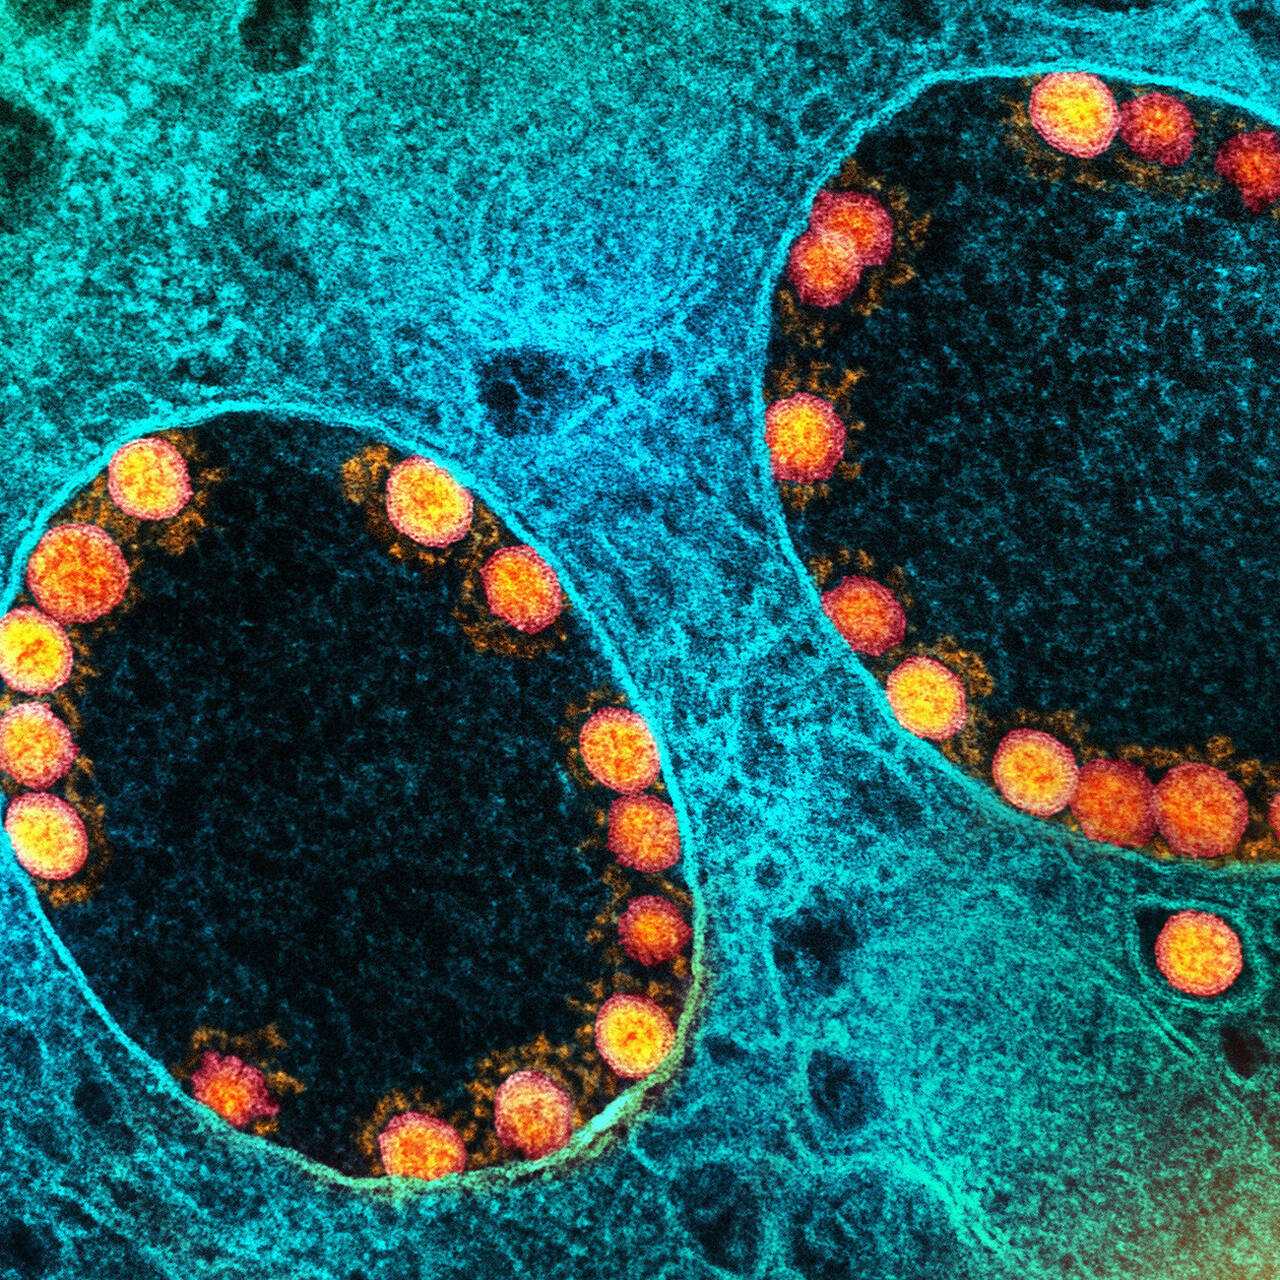

Фотографии объектов и элементов, связанных с цифрой 3

Раздел: Картинки на заметку